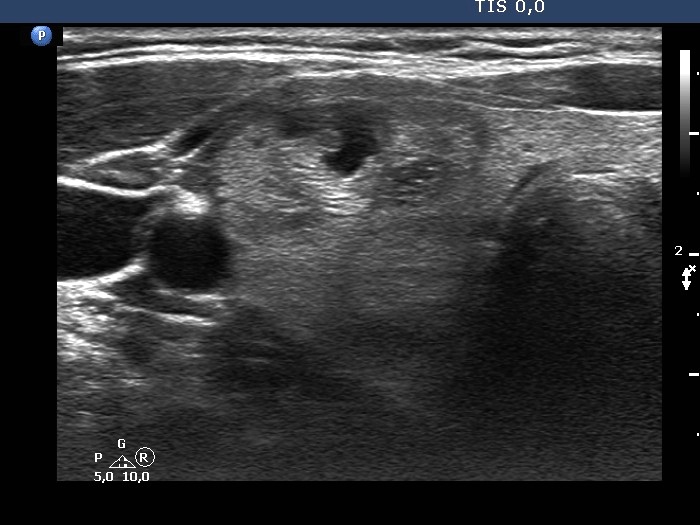

Ultrasonography. The thyroid was composed of numerous discrete lesions of various echogenicities. There was a partly cystic nodule in the upper-ventral part of the right lobe. The left lobe contained several cystic areas having comet tail artifacts.